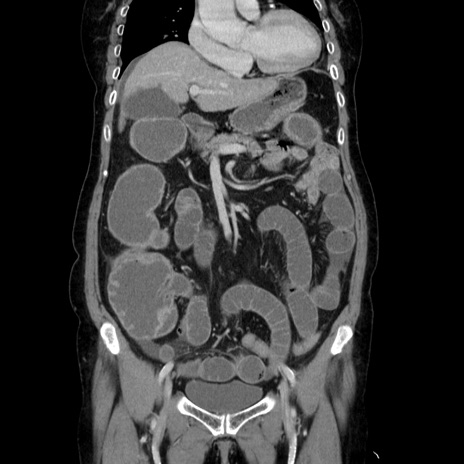

症例5(冠状断像)

【症例】70歳代女性

【主訴】お腹が張る

【現病歴】1週間くらい前から腹部膨満の自覚あり。昨日夜から増悪したため、本日救急外来受診。

【身体所見】意識清明、BT 36.5℃、BP 165/106mmHg、HR 80bpm、SpO2 98%、腹部:膨満、軟、自発痛・圧痛なし、触診にて不快感あり、腸蠕動音:減弱

【データ】WBC 12600、CRP 1.04